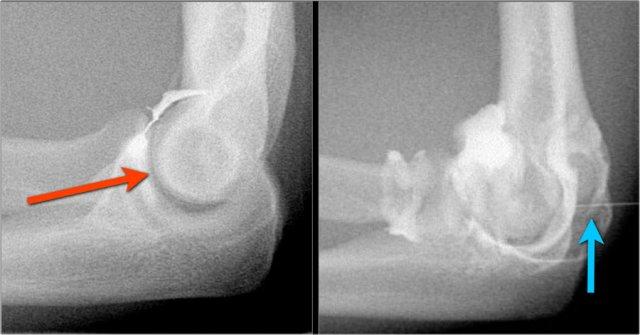

Thông thường khớp quay-chỏm được chọc từ phía ngoài với bệnh nhân nằm sấp và cánh tay gấp 90 độ trên đầu (mũi tên đỏ).

Tuy nhiên, điều này đôi khi có thể gây ra vấn đề nếu bạn quan tâm đến các dây chằng bên và bạn tiêm lidocaine hoặc thuốc cản quang vào các dây chằng này.

Vì vậy, gần đây chúng tôi bắt đầu sử dụng đường tiếp cận phía sau vào hố mỏm khuỷu (mũi tên xanh).

Gadolinium pha loãng được tiêm, tức là 0,05cc + 10cc nước muối sinh lý (sử dụng “ngoài chỉ định” tại Hoa Kỳ).